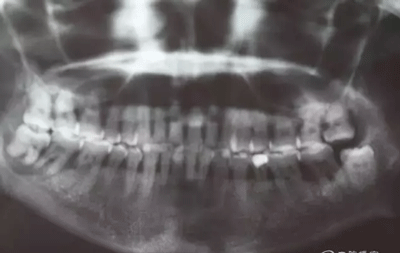

患者,白xx,女,40歲。主訴:右側(cè)下后牙牙探針齦反復(fù)腫痛,不能吃東西數(shù)月。??茩z查:48松動(dòng)Ⅲ,47松動(dòng)Ⅱ,牙周探針:48牙周袋均8mm,47遠(yuǎn)中牙周袋8mm,x全景片檢查:48牙槽骨弧形吸收至根尖區(qū),陰影較大。47遠(yuǎn)中牙槽骨吸收至遠(yuǎn)中根尖部,近中牙槽骨部分角形吸收。診斷:拔除48,試保留47.同期實(shí)行47牙周刮治術(shù)?;颊咄庵委煼桨?,簽知情同意書(shū)。